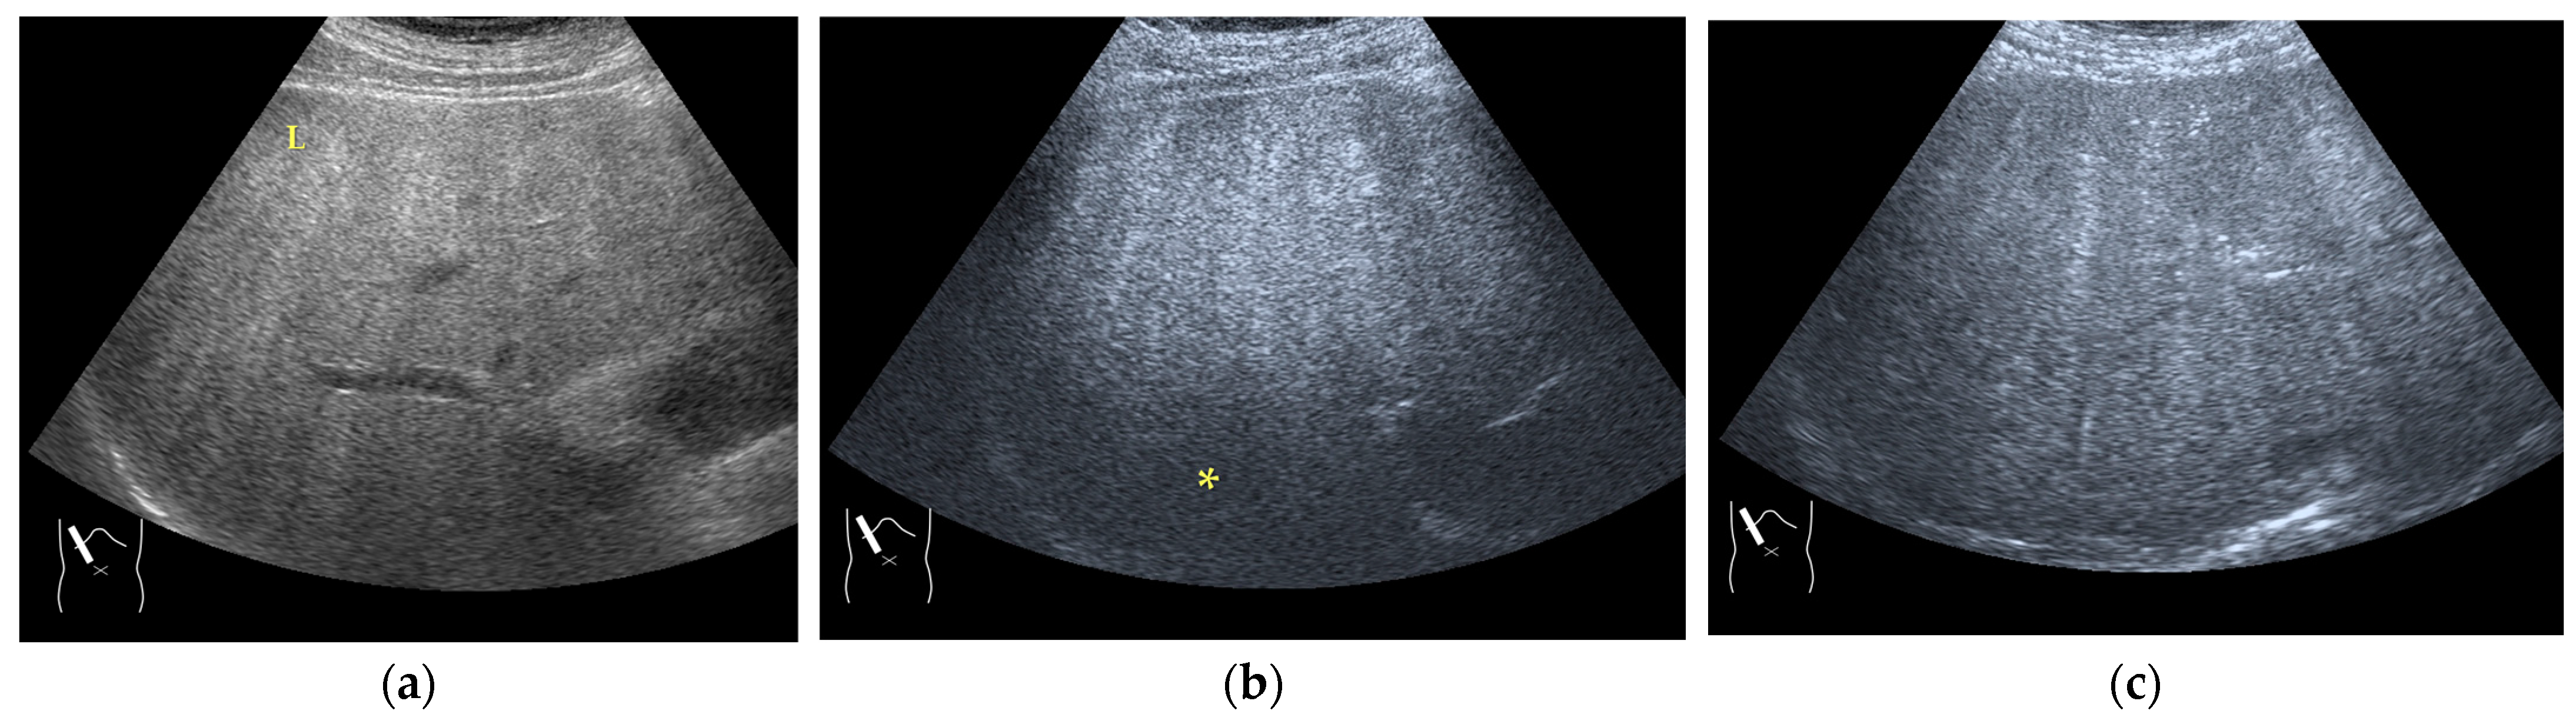

3.1.1. Refraction Artifacts

- Naganuma, H.; Ishida, H.; Uno, A.; Nagai, H.; Ogawa, M.; Kamiyama, N. Refraction artifact on abdominal sonogram. J. Med. Ultrason. 2021, 48, 273–283. [Google Scholar] [CrossRef]

- Uno, A.; Ishida, H.; Konno, K.; Hamashima, Y.; Naganuma, H.; Komatsuda, T.; Sato, M.; Watanabe, S. Post-tumoral distorted vascular images: Diagnostic problem of sonogram. J. Med. Ultrason. 2001, 28, 89–96. [Google Scholar] [CrossRef]